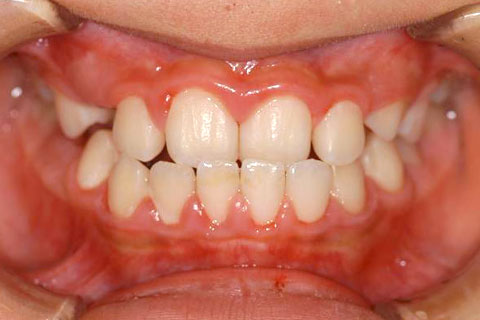

受け口(反対咬合)の症状

下あごが上あごより突出しているか、上あごが下あごより後退している状態で、咬み合わせが逆になっているので反対咬合ともいいます。お子様の場合、受け口(反対咬合)を放置していると、成長期において下あごが過大に成長し悪化しますので、出来る限り早い時期に治療することをおすすめします。受け口(反対咬合)は見た目の問題だけでなく顎の動きを制限し、将来的に顎の痛み(顎関節症)を引き起こす場合があります。また、お子様の場合は、正常な上顎の成長を阻害する可能性があります。

受け口(反対咬合)の症例